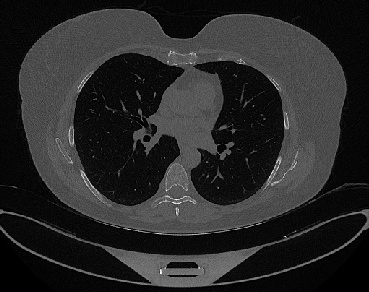

Figure 1 shows four CT scan slices, two from a non-COVID-19 CT scan, on the left and two from a COVID-19 scan, on the right. Bilateral ground glass regions are seen especially in lower lung lobes in the COVID-19 slices.